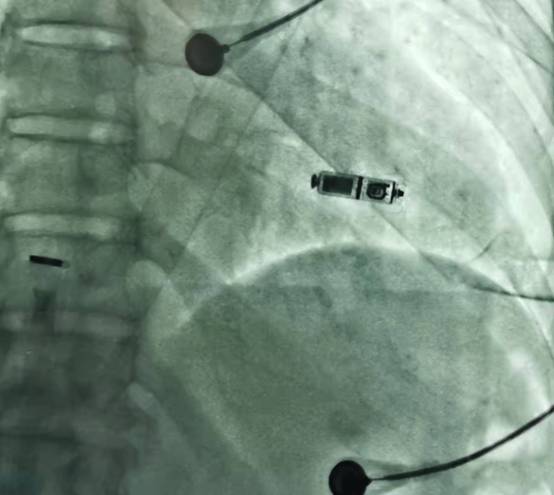

2022-01-28瑞安市人民医院成功完成2022年Micra首例植入,本中心第三例植入。无导线起搏新技术独立持续开展标志着我院心内科心律失常诊治水平省内一流、全国典范水准。

患者多次因心动过缓而出现头晕、黑朦等脑供血不足的症状。入院后心电图以及食道调搏提示为窦性停搏伴间歇房颤,瑞安市人民医院的叶向阳主任团队经过术前缜密诊疗方案分析,同患者和家属进行了充分的沟通后,选择了美敦力公司研发的Micra无导线起搏器进行植入。该起搏器无需植入心内膜导线,也无需在胸前皮下制作囊袋放置脉冲发生器(起搏器),减少了创伤与感染风险。而且Micra无导线起搏器直接植入在心腔内,无伤疤、无切口,患者在植入后几乎感觉不到起搏器的存在,大大改善了患者的生存质量。

Micra无导线起搏器的手术在局部麻醉下进行,通过股静脉穿刺,将起搏器通过导管植入到心腔内部,手术时间仅有30分钟,患者术后反应良好,预计术后48H即可恢复正常的工作和生活。

传统起搏器是治疗心动过缓的一线手段,自该技术问世以来,就为无数患者解除了病痛,使其重拾美好生活的信心。和传统起搏器不同,Micra创新的无导线,无囊袋设计,可以大大减少并发症发生的风险。相较于传统起搏器,Micra体积减小了93%,仅有维生素胶囊大小,重量仅约2g。Micra拥有超强的电池续航能力寿命超过12年,同时兼容1.5T(特斯拉)/3.0T核磁共振扫描的创新功能,可以为心脏提供持续稳定的动能。